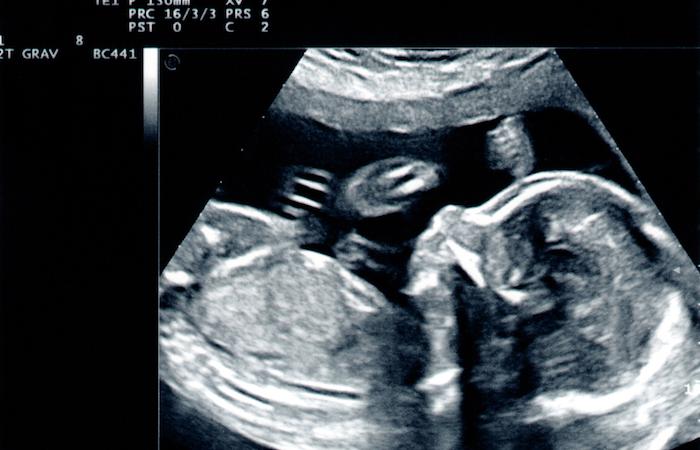

Le cycle infernal se poursuit pour le couple Delage. Originaires de Boulogne-sur-Mer (Pas-de-Calais), les jeunes parents ont découvert après huit mois de grossesse que leur enfant à naître souffrait d'une malformation cérébrale grave. Mais l'interruption médicale de grossesse (IMG) qu'ils avaient décidée a échoué. Si le bébé est donc né bien vivant, son état est jugé inquiétant, affirme Le Courrier Picard. Lors d'un examen médical de contrôle, l'équipe du CHRU de Lille a livré un pronostic pessimiste.

L'injection de médicaments via le cordon ombilical, lors de l'IMG, a fortement dégradé l'état de santé du bébé, déjà fragile. « On nous a indiqué que des taches étaient apparues sur la partie du cerveau qui n’était pas touchée, confie Jérôme Delage à nos confrères. Selon les médecins, l’arrêt cardiaque a privé le bébé d’oxygène et cela rend notre enfant inopérable alors qu’avant, on aurait pu tenter quelque chose. »

Pour les époux Delage, la situation est ubuesque depuis l'échec de l'avortement thérapeutique. Pour rappel, l'IMG a consisté en deux injections censées être fatales pour le fœtus. Mais quelques heures après, au moment de l’accouchement, le bébé du couple est né vivant. Autre surprise de taille pour les médecins et les parents : à la naissance, le bébé présentait moins de handicap que prévu. Il était en effet capable de bouger et de boire.